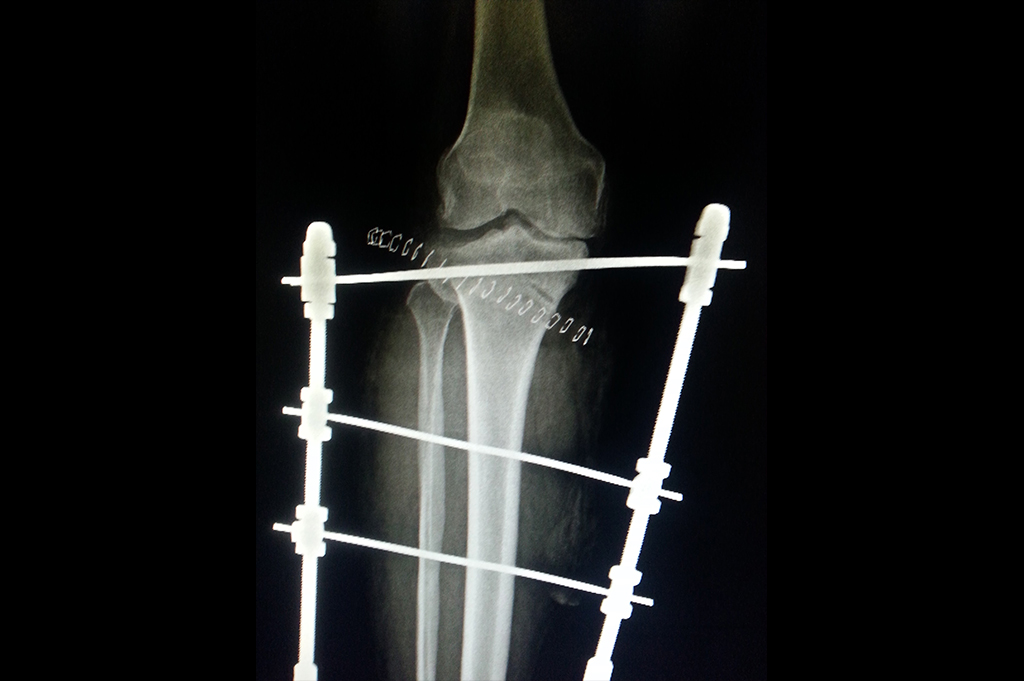

Deformity Correction - Genu Valgum